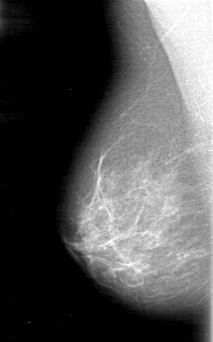

D_4054_1.LEFT_CC

RIGHT_MLO LINES 5116 PIXELS_PER_LINE 3181 BITS_PER_PIXEL 12 RESOLUTION 43.5 NON_OVERLAY